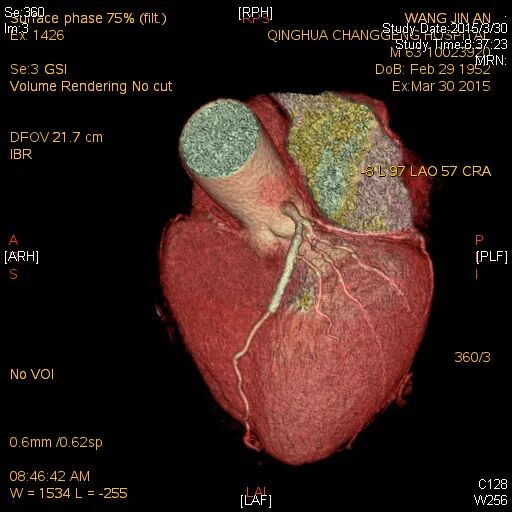

检查结果-CTA

LM未见异常,LAD原支架内血流通畅,支架近端可见局限性偏心狭窄90%,中远段未见狭窄或闭塞,前向血流TIMI-3级;中间支近中段弥漫性狭窄50%-60%。

LCX近段、中段、远段及分支均未见狭窄或闭塞,前向血流TIMI-3级。

RCA原支架内100%闭塞,前向血流TIMI-0级;可见LAD向RCA发出侧支,侧支血流1级。